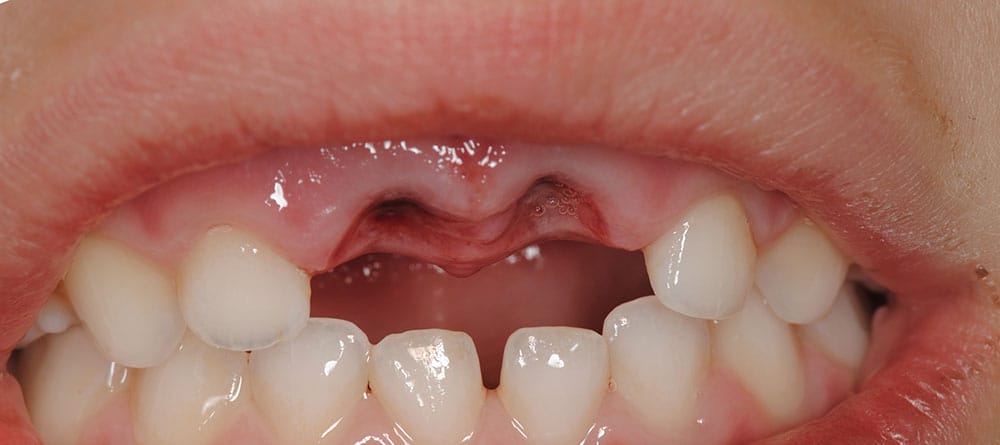

Negligencia en el tratamiento de traumatismos dentales

Mala Praxis en el Manejo de Traumatismos Dentales

Los traumatismos dentales requieren atención rápida y precisa para evitar complicaciones a largo plazo. Sin embargo, una mala praxis en su manejo puede agravar la lesión, causando pérdida dental, infecciones o daños en los tejidos circundantes.

Los errores más comunes incluyen diagnósticos incorrectos, falta de estabilización de piezas afectadas, tratamientos inadecuados o la omisión de controles posteriores. Esto puede derivar en necrosis pulpar, movilidad dental, infecciones o incluso la necesidad de extracciones innecesarias.